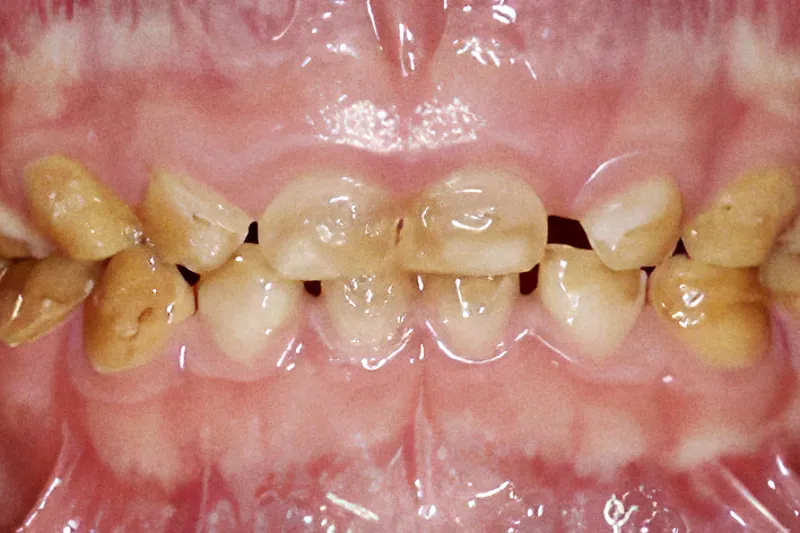

De hyppigst forekommende genetisk betingede afvigelser i tanddannelsen er amelogenesis imperfecta og dentinogenesis imperfecta, hvor dannelsen af henholdsvis emalje og dentin er blevet forstyrret. For afvigelser gælder, at både den primære og permanente dentition er afficeret, men med stor variation i fænotyper og behandlingsbehov. Det er bl.a. klinisk udfordrende, at kvaliteten af vævene kan være forringet, hvorved en basal egenskab som fx bindingsstyrken mellem tand og en restaurering også er nedsat. Dette betyder nedsat holdbarhed og højere omlavningsrate hos disse patienter og risiko for højere cariesprævalens. Det er derfor nødvendigt med særlig profylaktisk opmærksomhed. Det er vigtigt at kende til de forskellige typer af afvigelser for at kunne iværksætte optimal forebyggelse og relevant tandbehandling og vurdere, om henvisning til specialiseret oral rehabiliterende behandling er nødvendig.